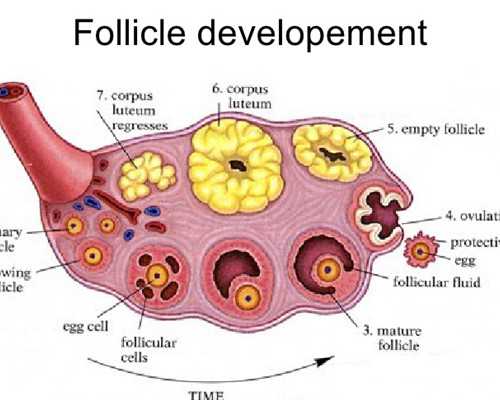

2.雌二醇很低到底有沒有關系,試管嬰兒,移植后

1)雌二醇偏低最直接的危害是導致女性不孕,因為它主要激發卵泡發育,同時血清雌二醇水平也間接上影響了卵巢功能,偏低則導致不排卵,影響生育;(2)女性的子宮、外陰、生殖道等器官的發育需要各類雌激素,如果雌二醇等激素水平降低則最終導致,女性子宮、外陰、生殖道萎縮;(3)雌二醇過低還會造成女性子宮內膜變薄,最終影響到月經量,直接影響到卵泡發育誘發不孕癥,除此外雌二醇偏低還會造成身體上出現一些更年期癥狀,如情緒不穩、失眠、潮熱、出汗等。盡早治療對于雌二醇增高有很好的調理作用,一般可通過一些雄激素類藥物來促使雌二醇恢復到正常水平。在做試管嬰兒之前醫生會根據患者的具體報告來進行診斷,是否能夠進行試管也需要根據患者自身的水平進行考慮。

5.雌二醇很低到底有沒有關系,試管嬰兒,移植后

1)雌二醇偏低最直接的危害是導致女性不孕,因為它主要激發卵泡發育,同時血清雌二醇水平也間接上影響了卵巢功能,偏低則導致不排卵,影響生育;(2)女性的子宮、外陰、生殖道等器官的發育需要各類雌激素,如果雌二醇等激素水平降低則最終導致,女性子宮、外陰、生殖道萎縮;(3)雌二醇過低還會造成女性子宮內膜變薄,最終影響到月經量,直接影響到卵泡發育誘發不孕癥,除此外雌二醇偏低還會造成身體上出現一些更年期癥狀,如情緒不穩、失眠、潮熱、出汗等。盡早治療對于雌二醇增高有很好的調理作用,一般可通過一些雄激素類藥物來促使雌二醇恢復到正常水平。在做試管嬰兒之前醫生會根據患者的具體報告來進行診斷,是否能夠進行試管也需要根據患者自身的水平進行考慮。

6.雌二醇很低到底有沒有關系,試管嬰兒,移植后

1)雌二醇偏低最直接的危害是導致女性不孕,因為它主要激發卵泡發育,同時血清雌二醇水平也間接上影響了卵巢功能,偏低則導致不排卵,影響生育;(2)女性的子宮、外陰、生殖道等器官的發育需要各類雌激素,如果雌二醇等激素水平降低則最終導致,女性子宮、外陰、生殖道萎縮;(3)雌二醇過低還會造成女性子宮內膜變薄,最終影響到月經量,直接影響到卵泡發育誘發不孕癥,除此外雌二醇偏低還會造成身體上出現一些更年期癥狀,如情緒不穩、失眠、潮熱、出汗等。盡早治療對于雌二醇增高有很好的調理作用,一般可通過一些雄激素類藥物來促使雌二醇恢復到正常水平。在做試管嬰兒之前醫生會根據患者的具體報告來進行診斷,是否能夠進行試管也需要根據患者自身的水平進行考慮。

3.雌二醇很低到底有沒有關系,試管嬰兒,移植后

1)雌二醇偏低最直接的危害是導致女性不孕,因為它主要激發卵泡發育,同時血清雌二醇水平也間接上影響了卵巢功能,偏低則導致不排卵,影響生育;(2)女性的子宮、外陰、生殖道等器官的發育需要各類雌激素,如果雌二醇等激素水平降低則最終導致,女性子宮、外陰、生殖道萎縮;(3)雌二醇過低還會造成女性子宮內膜變薄,最終影響到月經量,直接影響到卵泡發育誘發不孕癥,除此外雌二醇偏低還會造成身體上出現一些更年期癥狀,如情緒不穩、失眠、潮熱、出汗等。盡早治療對于雌二醇增高有很好的調理作用,一般可通過一些雄激素類藥物來促使雌二醇恢復到正常水平。在做試管嬰兒之前醫生會根據患者的具體報告來進行診斷,是否能夠進行試管也需要根據患者自身的水平進行考慮。

5.雌二醇很低到底有沒有關系,試管嬰兒,移植后

1)雌二醇偏低最直接的危害是導致女性不孕,因為它主要激發卵泡發育,同時血清雌二醇水平也間接上影響了卵巢功能,偏低則導致不排卵,影響生育;(2)女性的子宮、外陰、生殖道等器官的發育需要各類雌激素,如果雌二醇等激素水平降低則最終導致,女性子宮、外陰、生殖道萎縮;(3)雌二醇過低還會造成女性子宮內膜變薄,最終影響到月經量,直接影響到卵泡發育誘發不孕癥,除此外雌二醇偏低還會造成身體上出現一些更年期癥狀,如情緒不穩、失眠、潮熱、出汗等。盡早治療對于雌二醇增高有很好的調理作用,一般可通過一些雄激素類藥物來促使雌二醇恢復到正常水平。在做試管嬰兒之前醫生會根據患者的具體報告來進行診斷,是否能夠進行試管也需要根據患者自身的水平進行考慮。

6.雌二醇很低到底有沒有關系,試管嬰兒,移植后

1)雌二醇偏低最直接的危害是導致女性不孕,因為它主要激發卵泡發育,同時血清雌二醇水平也間接上影響了卵巢功能,偏低則導致不排卵,影響生育;(2)女性的子宮、外陰、生殖道等器官的發育需要各類雌激素,如果雌二醇等激素水平降低則最終導致,女性子宮、外陰、生殖道萎縮;(3)雌二醇過低還會造成女性子宮內膜變薄,最終影響到月經量,直接影響到卵泡發育誘發不孕癥,除此外雌二醇偏低還會造成身體上出現一些更年期癥狀,如情緒不穩、失眠、潮熱、出汗等。盡早治療對于雌二醇增高有很好的調理作用,一般可通過一些雄激素類藥物來促使雌二醇恢復到正常水平。在做試管嬰兒之前醫生會根據患者的具體報告來進行診斷,是否能夠進行試管也需要根據患者自身的水平進行考慮。

8.雌二醇很低到底有沒有關系,試管嬰兒,移植后

1)雌二醇偏低最直接的危害是導致女性不孕,因為它主要激發卵泡發育,同時血清雌二醇水平也間接上影響了卵巢功能,偏低則導致不排卵,影響生育;(2)女性的子宮、外陰、生殖道等器官的發育需要各類雌激素,如果雌二醇等激素水平降低則最終導致,女性子宮、外陰、生殖道萎縮;(3)雌二醇過低還會造成女性子宮內膜變薄,最終影響到月經量,直接影響到卵泡發育誘發不孕癥,除此外雌二醇偏低還會造成身體上出現一些更年期癥狀,如情緒不穩、失眠、潮熱、出汗等。盡早治療對于雌二醇增高有很好的調理作用,一般可通過一些雄激素類藥物來促使雌二醇恢復到正常水平。在做試管嬰兒之前醫生會根據患者的具體報告來進行診斷,是否能夠進行試管也需要根據患者自身的水平進行考慮。

10.雌二醇很低到底有沒有關系,試管嬰兒,移植后

1)雌二醇偏低最直接的危害是導致女性不孕,因為它主要激發卵泡發育,同時血清雌二醇水平也間接上影響了卵巢功能,偏低則導致不排卵,影響生育;(2)女性的子宮、外陰、生殖道等器官的發育需要各類雌激素,如果雌二醇等激素水平降低則最終導致,女性子宮、外陰、生殖道萎縮;(3)雌二醇過低還會造成女性子宮內膜變薄,最終影響到月經量,直接影響到卵泡發育誘發不孕癥,除此外雌二醇偏低還會造成身體上出現一些更年期癥狀,如情緒不穩、失眠、潮熱、出汗等。盡早治療對于雌二醇增高有很好的調理作用,一般可通過一些雄激素類藥物來促使雌二醇恢復到正常水平。在做試管嬰兒之前醫生會根據患者的具體報告來進行診斷,是否能夠進行試管也需要根據患者自身的水平進行考慮。